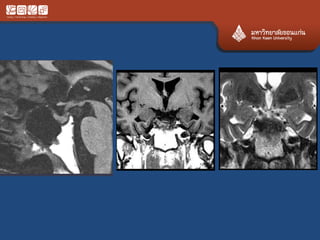

# chordoma

• Locally agreesive never metas

• Clivus, upper C, lower L, sacrum

• 70% at the midline

• Expansile, calcification, bright T2

• Ddx chondrosarcoma